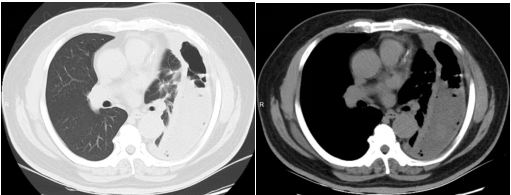

入院时CT显示:左侧胸腔被积液填满,如同一个巨大的"脓袋"压迫着正常肺组织。

棘手的是,传统穿刺引流如同"抽丝剥茧",抽出近2000ml腥臭脓液后,复查CT仍见残留大量纤维分隔包裹,配合强力抗生素治疗,患者仍然持续高烧不退。